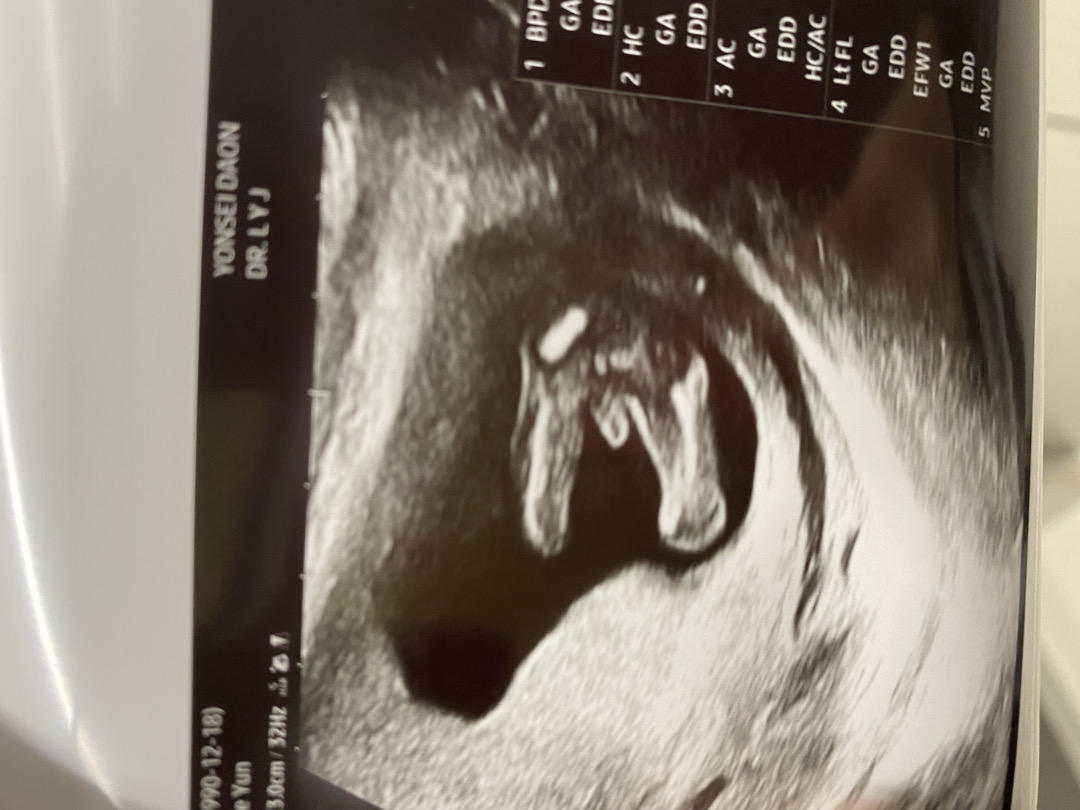

์ค๋ 15์ฃผ์ ์ ์ด๋ค์๋๋ฐ ๋ฐฐ๊ฐ ์๊พธ ๋น๊ฒจ์ ์ด์ํ๋ณด๋ฌ๊ฐ๋ค๊ฐ ์ฑ๋ณ์ ์์์ด์ใ ใ ใ ์ ์๋๊ป์ ์๋ค์ธ ๊ฒ ๊ฐ๋ค๊ณ ํ์๋๋ฐ ์ฑ๋ณ ํ์ ํ๊ณ ๋์ ๋จ ํ๋ฒ๋ ํ๋ฆฐ์ ์ด ์๋ค๊ณ ํ์๋ค์. ์ฌ๋ฌ๋ถ๋ค ๋์๋ ํ์คํ๊ฒ ๐ถ๏ธ๊ฐ ๋ณด์ด์๋์?ใ ใ ใ

๐ถ๏ธํ์ ์ด๊ฒ ์ฃ ?ใ ใ